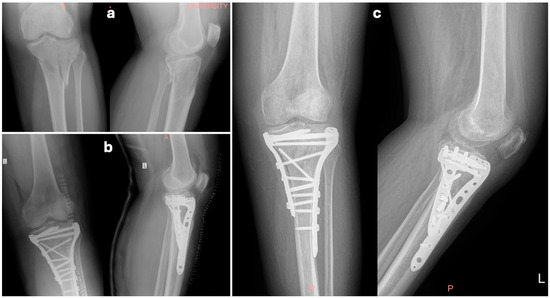

Comparative Outcomes of Single- Versus Dual-Incision Approaches for Open Reduction and Internal Fixation of Complex Tibial Plateau Fractures

Background/Objectives: Open reduction and internal fixation with plates and screws is the treatment of choice for bicondylar tibial plateau fractures. The use of a surgical approach remains a topic of debate regarding the site and number of incisions that ensure best access [...] Read more.

Background/Objectives: Open reduction and internal fixation with plates and screws is the treatment of choice for bicondylar tibial plateau fractures. The use of a surgical approach remains a topic of debate regarding the site and number of incisions that ensure best access for reduction with minimum additional soft tissue damage. This retrospective cohort study compared clinical, radiological, and functional outcomes of single- (anterior) versus dual-incision (anterolateral and medial) approaches that are widely used in the operative treatment of Schatzker V–VI tibial plateau fractures. Methods: Eighty-two patients treated between 2005 and 2020 were retrospectively analyzed. Fifty-two underwent a single-incision (SI) approach and 30 a dual-incision (DI) approach. Operative parameters, complications, reduction quality, Knee Society Score (KSS), Oxford Knee Score (OKS), and post-traumatic arthritis incidence were assessed. Results: Mean patient age was 50.6 years, with a mean follow-up of 8.5 years. Operative time was shorter in the SI group, though fluoroscopy time was longer. No significant difference was observed in reduction quality or wound complications. Post-traumatic arthritis occurred in 57.6% of SI and 53.3% of DI patients, with severe arthritis more frequent in SI (30% vs. 12.5%, p < 0.05). Seven patients required conversion to total knee arthroplasty (five SI, two DI). Functional recovery was similar: mean KSS 68.6% (SI) vs. 70.5% (DI) and OKS 36.1 vs. 40.8 (p > 0.05) at 5 years. Conclusions: Both single- and dual-incision approaches for complex tibial plateau fractures provide satisfactory long-term outcomes. While differences in complications and arthritis rates were minor, surgical choice should be guided by the fracture morphology, patient characteristics, and surgeon’s experience to balance reduction quality with soft tissue preservation. Full article

Figure 1